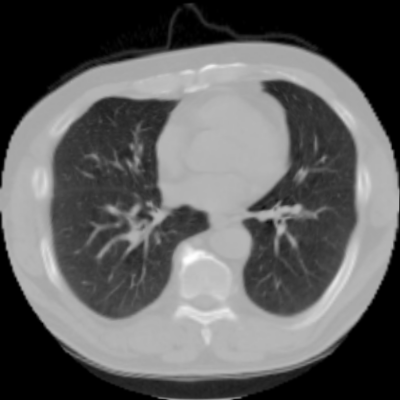

We now consider applying the proposed image registration method on real lung CT images retrieved from the National Lung Screening Trial (NLST) dataset [1]. Fig. 9(a) and Fig. 9(b) show two slices of lung CT images that we use as the source and the target (see Fig. 9(c) for the absolute intensity difference). We remark that the CT images are originally with different intensity, and so we apply an intensity histogram matching before running the registration experiment. Fig. 9(d) shows the registration result obtained by our proposed method. It can be observed that our method successfully produces a large deformation on the right lung of the source image to match that of the target image (see also Fig. 9(e) for the final absolute intensity difference). On the contrary, DDemons [47] (Fig. 9(f)), LDDMM [5] (Fig. 9(g)), Elastix [29] (Fig. 9(h)) and DROP [18] (Fig. 9(i)) all fail to produce an accurate and bijective registration result. This shows that our method is more capable of handling large deformation image registration.

We then test our method on slices of chest CT images obtained from the Open Access Biomedical Image Search Engine [2]. Fig. 10(a) and 10(b) show the source image and target image respectively, and the intensity difference is shown in Fig. 10(c). The registration result obtained by our proposed method is shown in Fig. 10(d) (see also the result with the deformed underlying grid in Fig. 10(e)). From the final intensity difference plot in Fig. 10(f), it is easily to see that our method matches not only the two large components but also the small dot at the center very well. On the contrary, DDemons [47] produces a suboptimal registration result with a significantly larger mismatch of the small component at the center (see Fig. 10(g) and Fig. 10(h)).